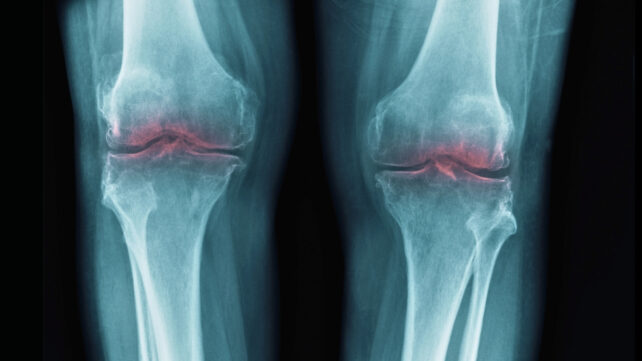

Osteoarthritis is a prevalent degenerative joint condition characterized by discomfort, rigidity, and effusion, leading to diminished joint mobility. While frequently impacting the knees, hips, and hands, it can manifest in other bodily articulations.

When contrasted with inactivity and placebo interventions, exercise was associated with modest improvements in pain reduction for the hip, knee, and hand, registering between 6 and 12 points on a 100-point scale.

For osteoarthritis affecting the knee and hip, evidence suggested that exercise yielded comparable pain reduction and functional improvement to pharmacological interventions like ibuprofen and intra-articular corticosteroid injections aimed at mitigating inflammation. These pharmaceutical approaches also achieved pain alleviation in the vicinity of 5–10%.